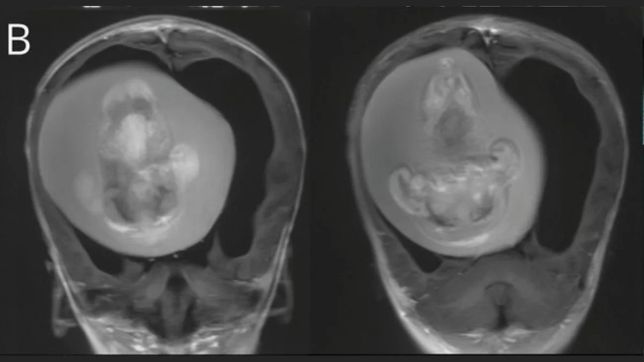

Uma menina de 1 ano passou por uma cirurgia delicada para retirar um feto do cérebro.

O embrião ficou alojado no crânio da criança chinesa enquanto ambos se desenvolviam no útero da mãe, em uma condição extremamente rara conhecida como fetus in fetu (gêmeo parasitário).

O feto foi descoberto quando os pais da menina procuraram o hospital para investigar porque a criança tinha o volume da cabeça aumentado e apresentava dificuldades motoras.